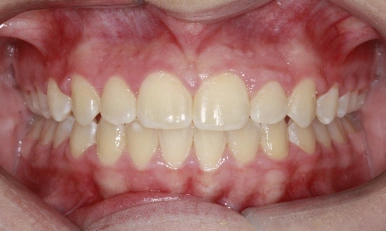

Patient Results